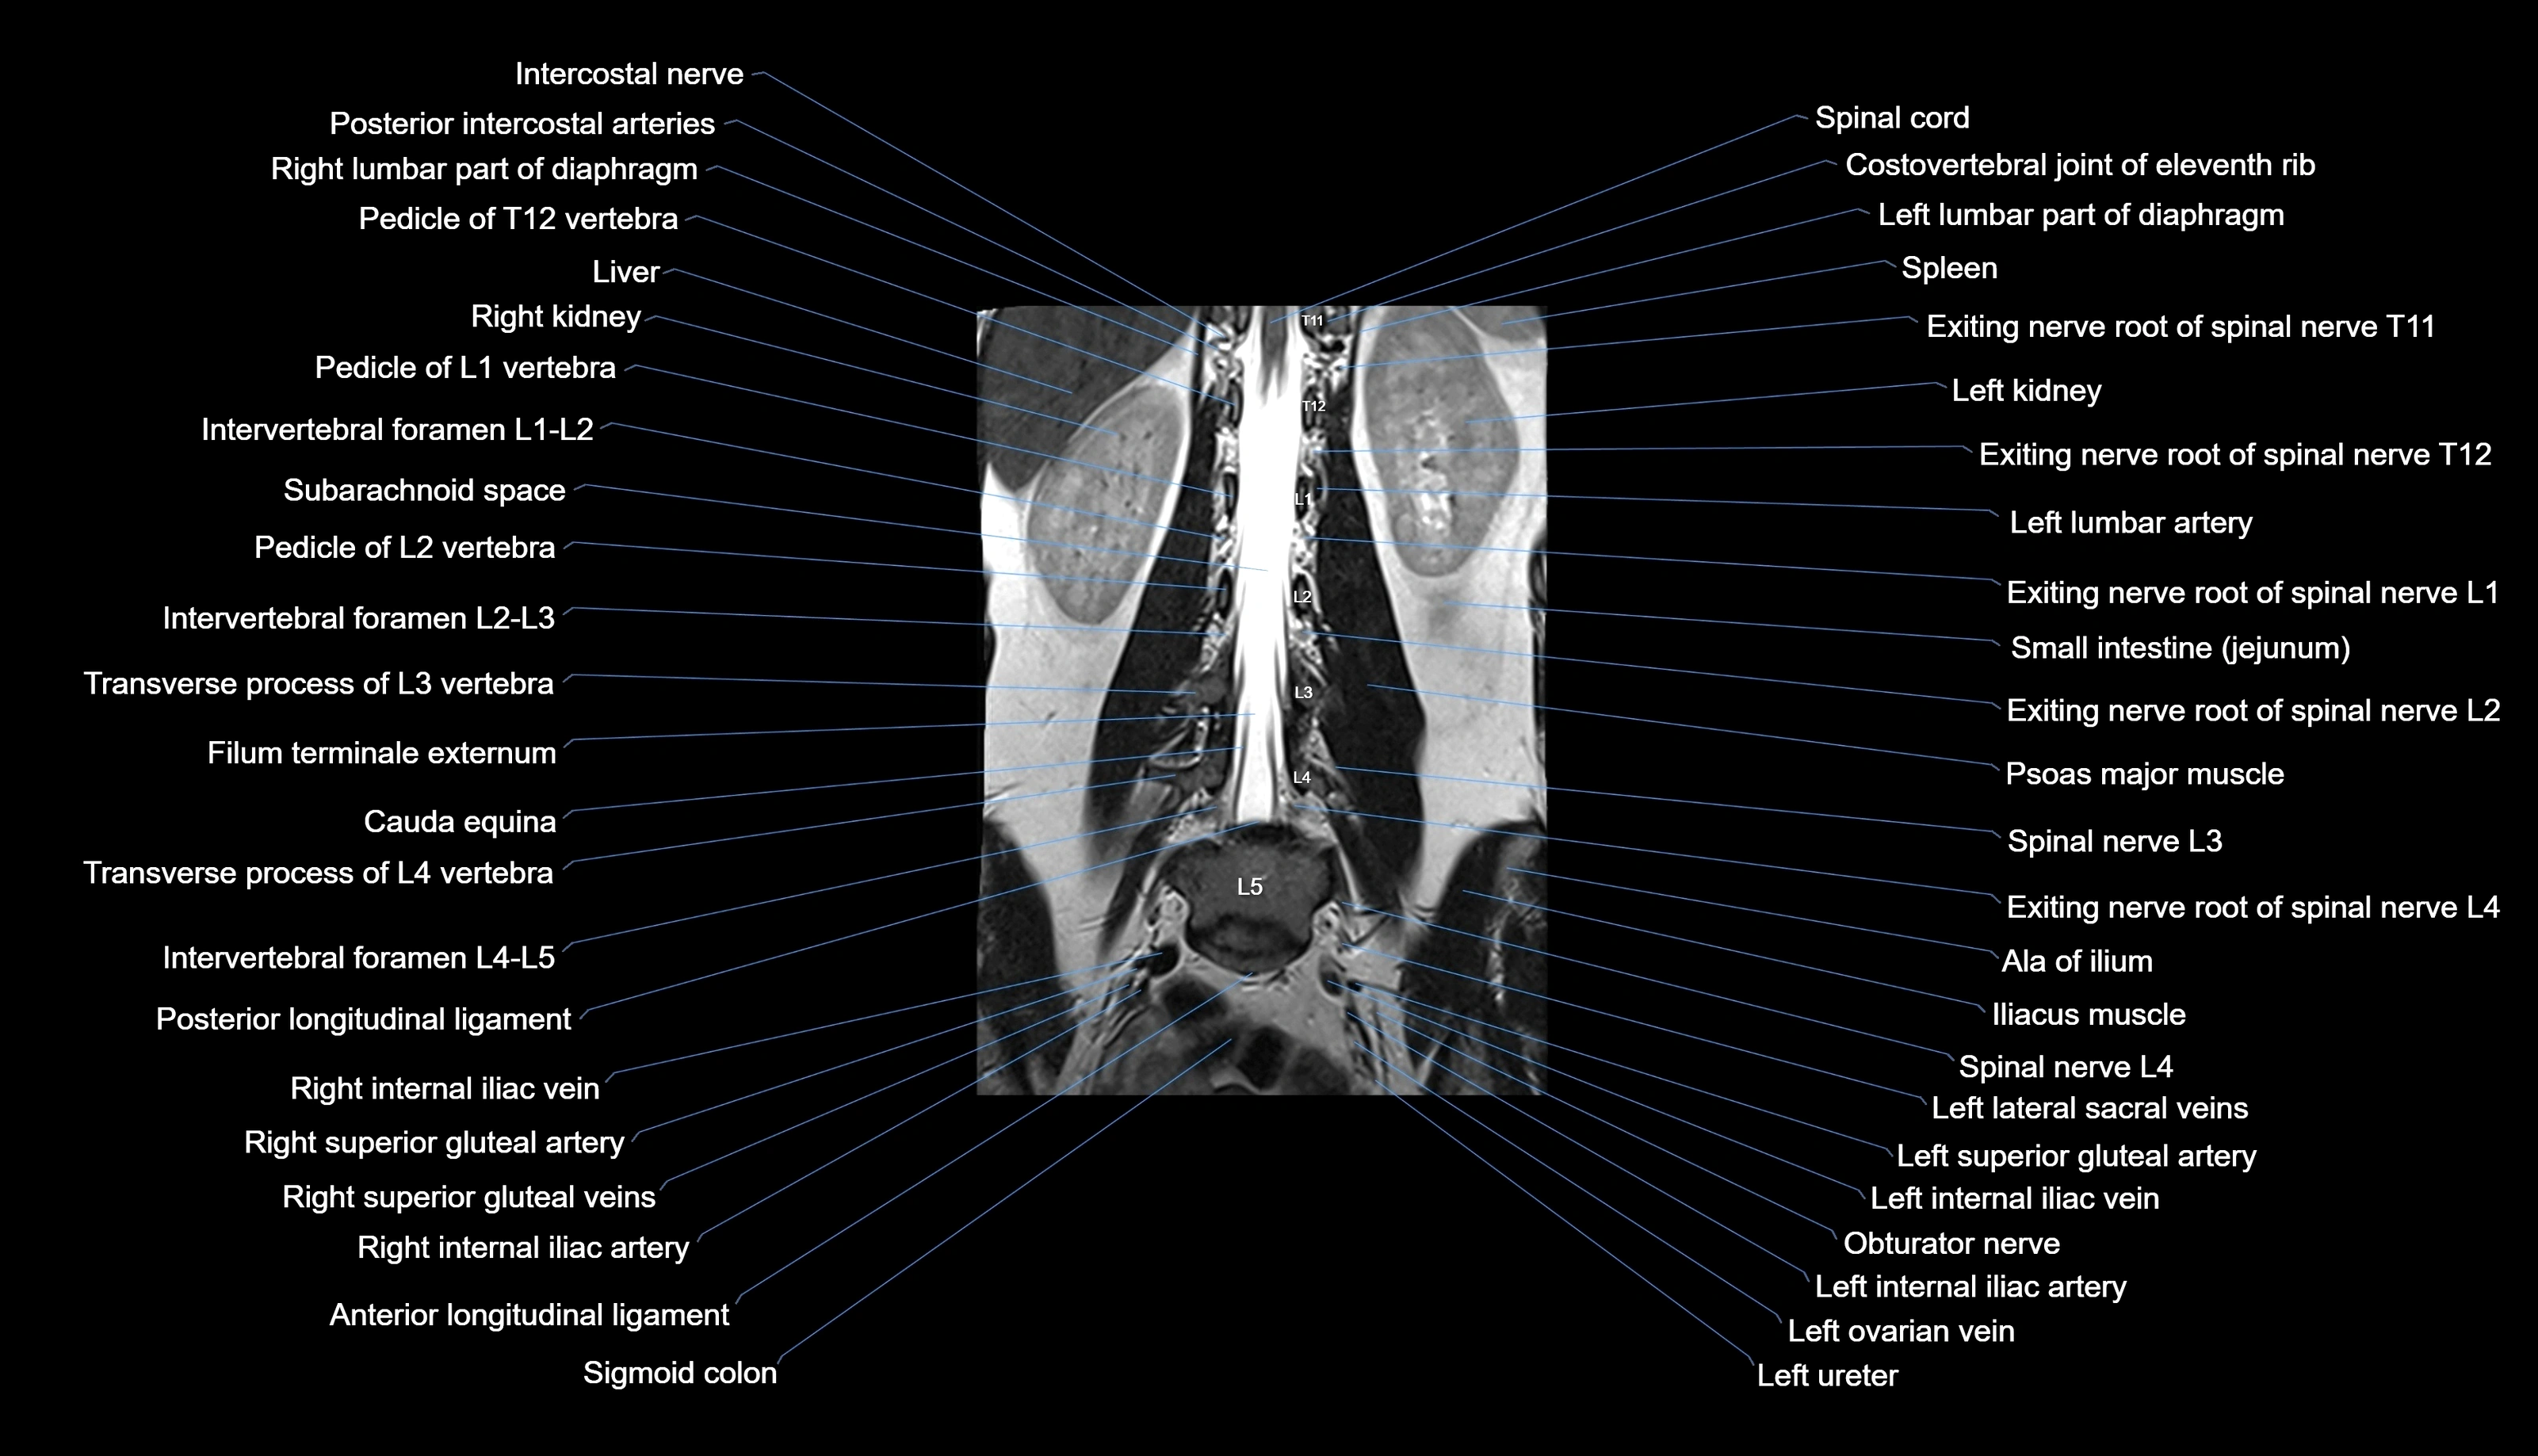

MRI images